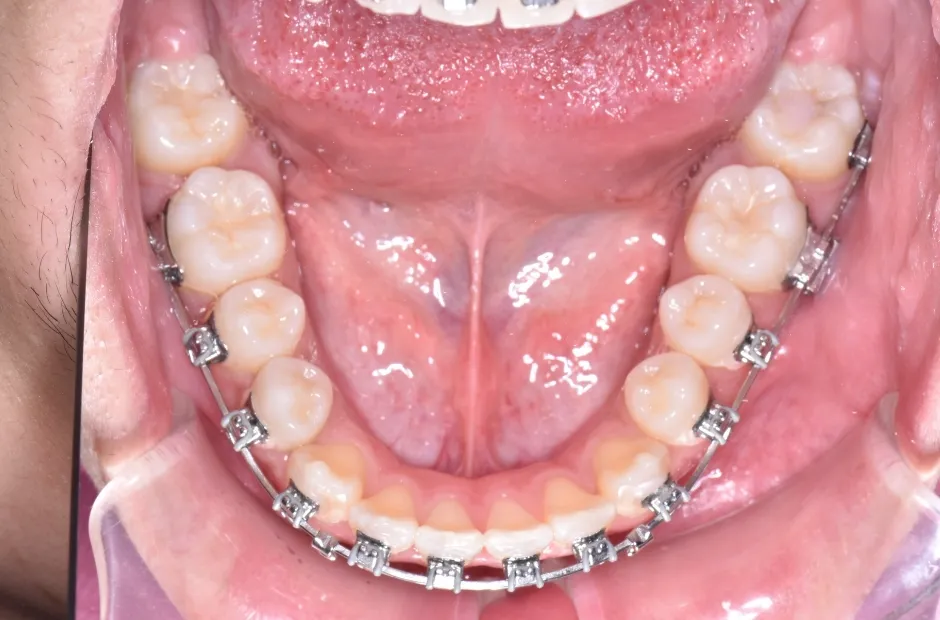

叢生

| 診断名・主訴 | 叢生 |

|---|---|

| 年齢・性別 | 43歳・女性 |

| 治療期間・回数 | 2年7か月 27回 |

| 治療に用いた主な装置 | 舌側矯正 |

| 抜歯部位 | 両顎4,4 |

| 治療費 | 100万円(税抜) |

| リスク・副作用 | 装置による違和感・疼痛・歯肉退縮・歯根吸収・虫歯のリスクなど |

治療前

治療中

治療後